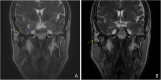

Case presentation: This case report describes a large chondroblastoma (diameter, approximately 37 mm) that occurred in the TMJ. The tumor was sufficiently aggressive to destroy the TMJ, mandibular condyle neck, external auditory canal (EAC), mandibular fossa of the temporal bone, and facial nerve. The tumor was completely excised using a pre-auricular approach. The EAC and surgical defect were successfully reconstructed using a temporoparietal fascia flap (TPFF) and an inguinal free fat graft. There was no local tumor recurrence at the 18-month follow-up visits. However, the patient developed sensory neural hearing loss, and his eyebrow paralysis worsened, eventually requiring plastic surgery.